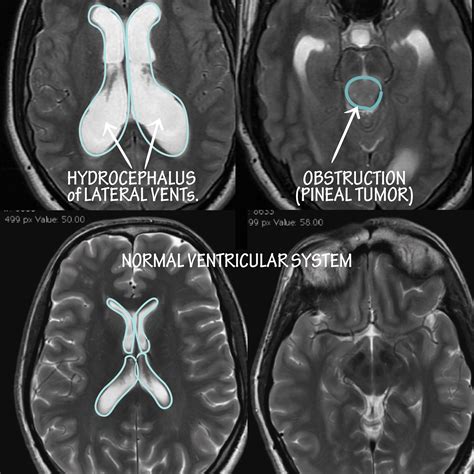

Hydrocephalus is a condition characterized by the accumulation of cerebrospinal fluid (CSF) in the brain, leading to increased intracranial pressure. Among the various types of hydrocephalus, Non Communicating Hydrocephalus is a significant subtype that requires careful understanding and management. This condition, often referred to as Non Communicating Hydrocephalus Amboss, involves an obstruction within the ventricular system of the brain, preventing the normal flow of CSF. This blog post delves into the intricacies of Non Communicating Hydrocephalus, its causes, symptoms, diagnosis, and treatment options.

Non Communicating Hydrocephalus, also known as obstructive hydrocephalus, occurs when there is a blockage in the pathways that allow CSF to flow within the brain. This blockage can be caused by various factors, including tumors, infections, congenital malformations, or head injuries. Unlike communicating hydrocephalus, where the obstruction is outside the ventricular system, non-communicating hydrocephalus specifically affects the ventricles themselves.

• Tumors: Brain tumors, especially those located in the posterior fossa or near the ventricles, can obstruct the flow of CSF.

• Imaging Studies: Imaging techniques such as computed tomography (CT) scans and magnetic resonance imaging (MRI) are crucial for visualizing the brain and identifying any obstructions or abnormalities in the ventricular system.